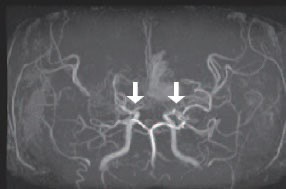

모야모야병은 뇌기저부의 주요 혈관이 서서히 협착되고 막히면서 뇌혈류가 감소하는 만성 진행성 뇌혈관 질환입니다. 협착이 진행된 부위를 대신해 뇌는 생존을 위해 얇고 약한 혈관망을 만들어 혈류를 보충하려 하고, 이 새로운 혈관들이 촬영 영상에서 연기처럼 퍼져 보인다고 하여 ‘모야모야’라는 이름이 붙었습니다. 기전적으로는 내경동맥 말단부와 중대뇌동맥·전대뇌동맥의 기시부에 병변이 가장 잘 생기며, 시간이 지남에 따라 양쪽에 대칭적으로 나타나는 특징을 보였습니다. 이 질환은 단순한 혈관 협착이 아니라 진행성 변화이기 때문에 치료하지 않으면 혈류 부족이 심해지고 뇌 손상이 누적될 수 있습니다. 또한 뇌기능이 체력·호흡·체온 변화 등에 민감하게 반응하기 때문에 과호흡, 울음, 격렬한 운동, 감염 등으로 증상이 악화될 수 있습니다. 즉, 모야모야병은 시간이 지나면서 뇌혈류를 감소시키고 뇌졸중 위험을 높이는 질환이며, 평생 관리가 필요한 만성적 특성을 갖고 있습니다.

따라서 가족력이 있거나 의심되는 증상이 있다면 뇌 MRA·MRI 등의 정기검진이 도움이 되며, 조기 진단 시 치료 효과도 훨씬 높아집니다.

수술치료(뇌혈류 재건술, Revascularization surgery)

모야모야병의 핵심 치료는 뇌혈류 공급을 위한 새로운 통로를 만들어주는 수술입니다.

① 직접 우회술(Direct bypass)

• 측두동맥(STA)을 직접 뇌혈관(MCA)과 연결해 혈류를 즉시 공급하는 방식 • 성인에서 가장 많이 시행